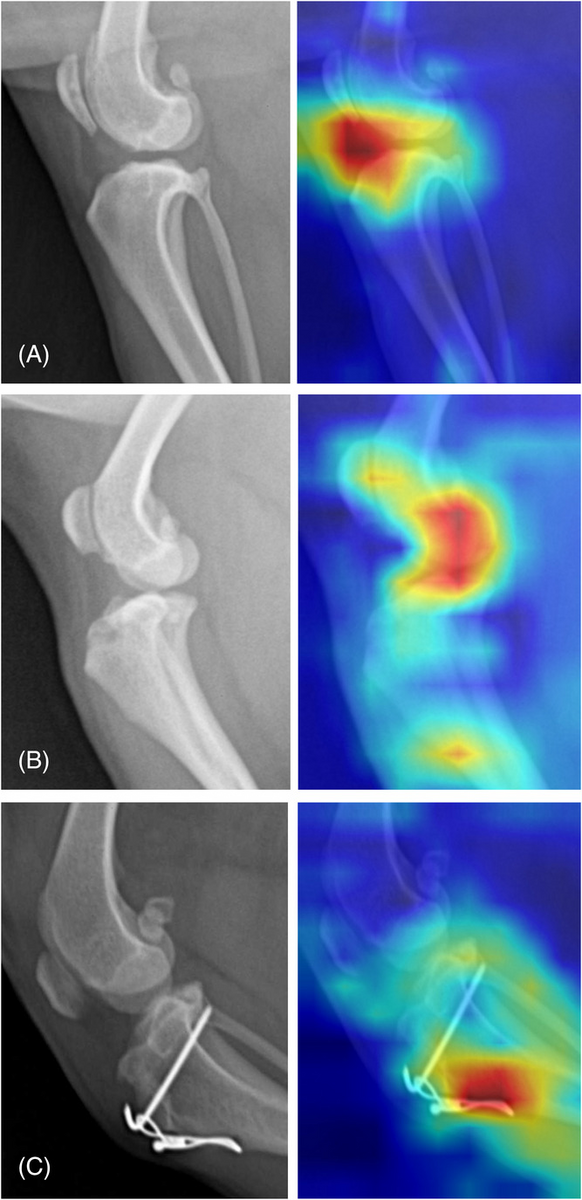

Can AI identify stifle disease in dogs?

VRU 64(1): 113-122